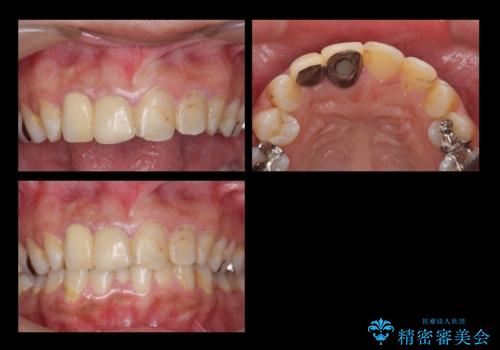

- 前歯の被せもののやり直しを希望して来院。

隣の歯もつぎはぎでプラスチックが劣化していたため、虫歯を取りセラミックでかぶせました。

保険治療の前歯の被せものの縁(マージン)が歯茎の中まで及んでいたため、歯周外科手術を行い、マージンが歯肉縁下深くならないように設定しました。

- 63.8万円(右上4~左上2:emaxクラウン 7万円x6本、仮歯 1万円x6本、歯周外科手術 15万円、右上1:精密根管再治療 9万円およびファイバーコア2万円)費用は治療当時の料金となります

右上1番は、根の治療のやり直しをしています。